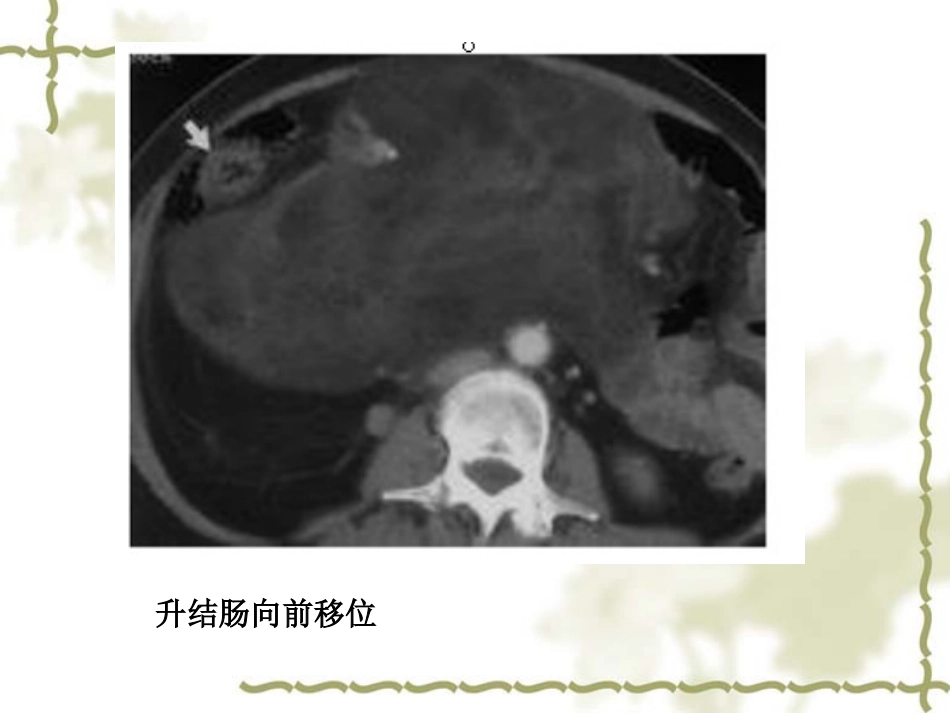

腹膜后神经源性肿瘤Retroperitonealneurogenictumors赵亚波腹膜后间隙肿块:(1)肿块使腹膜后脏器移位,尤其是向前移位。(2)肿块与腹膜后脏器分界不清,脂肪间隙消失,但肿块最大径线仍在脏器之外。(3)主动脉或下腔静脉受累或包埋。(4)肿块使腹腔内脏器向前方或侧方移位,但其间的脂肪间隙仍存在。(5)巨大肿块,其前缘因壁层腹膜(或同时有肾前筋膜)的被覆作用而多显光整,即使接近或抵达前腹壁,二者间仍可见窄带状或新月形低密度影,此可与腹腔内肿瘤鉴别。升结肠向前移位鸟嘴征:当肿块破坏一个器官的边缘呈鸟嘴状。而临近的器官有一个钝性的边缘,说明肿块压迫器官而不是起源于它。概述神经源性肿瘤在原发性腹膜后肿瘤中占第二位,仅次于间叶组织来源肿瘤。神经源性肿瘤多起源于脊柱两旁、盆腔骶前,发病隐蔽,早期出现不规则的疼痛症状,无特异性。腹膜后组织间隙较大,器官相对少,肿瘤临床症状出现迟,因此,腹膜后神经源性肿瘤体积较大。分类:腹膜后神经源性肿瘤神经鞘膜来源神经鞘瘤神经纤维瘤恶性神经鞘瘤恶性神经纤维瘤交感神经节来源神经节细胞瘤神经节母细胞瘤神经母细胞瘤副神经节瘤功能性无功能性腹膜后神经鞘瘤是最常见的腹膜后良性肿瘤,肿瘤生长缓慢。可发生于任何年龄,20-50岁多见,无明显的性别差异;大部分患者是因为体检或其他症状就诊时发现。起源于神经鞘膜雪旺氏细胞;组织学主要由排列紧密的AntoniA组织及细胞疏松而富含脂质,黏液样基质的AntoniB组织构成。大多位于脊柱周围的腹膜后间隙内;常有包膜;可伴有出血、囊变及钙化。CT表现密度不均;T1WI呈低信号,T2WI呈不均匀高信号。增强扫描:典型表现为进行性延迟强化。(会因病理类型的不同而有相应变化)如发现肿瘤与神经相连或与椎间孔关系密切,则对诊断有重要意义。肿块边缘光滑,密度不均匀,其内可见多发囊变、坏死区域,分布不规则;肿块不均匀强化,周围脏器受推压移位。病理:恶性神经鞘瘤伴横纹肌肉瘤分化(即恶性蝾螈瘤MTT)恶性蝾螈瘤(MTT)MTT是一种极少见的含有成横纹肌细胞分化的恶性神经鞘瘤,肿瘤内的神经成分可以向骨骼肌方向分化,同蝾螈的正常神经也能向骨骼肌方向分化的特性类似,故命名为“蝾螈瘤”。MTT应完全具备3条标准:①肿瘤起源于周围神经或发生于I型神经纤维瘤病;②以恶性神经鞘膜瘤为主要成分;③出现真正的肿瘤性横纹肌母细胞。MTT的诊断依赖于病理及免疫组化确定神经鞘细胞和横纹肌母细胞成分则可确诊。神经纤维瘤可发生于任何年龄。外观呈圆形或梭形,常无包膜,可见神经纤维穿过肿瘤实质。可伴有粘液变性。组织学显示肿瘤主要由纤维细胞及Schwan细胞构成。神经纤维瘤术后可以复发也可以恶变,表现为轮廓和边缘不清,密度/信号不一,瘤周脂肪间隙模糊,表现为囊状多个团块状肿物。神经节细胞瘤(GN)可发生于任何年龄,多见于青年及成年人,大部分患者在10岁以上。沿交感神经链分布,常位于脊柱两旁。病理:主要由大量的黏液基质成分,神经节细胞、雪旺氏细胞组成。多表现为境界清楚的椭圆形或梭形软组织影,CT值较低,包膜完整;少有出血、坏死或囊变,少数可见钙化。T1WI低信号,T2WI不均匀高信号。病灶可沿间隙呈膨胀性及嵌入式生长,或对周围血管呈包绕改变,但无侵犯血管征象;多为均匀轻度进行性强化。神经母细胞瘤(NB)婴幼儿多见。完全由神经母细胞及数量不等的神经纤维丝组成,没有节细胞及施万细胞间质组成。恶性程度高,肿瘤向周围浸润性生长。肿块较大,形态不规则,密度不均匀,中间有明显囊变坏死,无定形显著钙化是其特征性表现,增强扫描实性成分明显强化。神经节母细胞瘤(GNB)GNB属于儿童异质性实体肿瘤,其预后与神经母细胞和节细胞的比例有关,神经母细胞成分较少而节细胞较多,则预后较好。很难与神经母细胞瘤鉴别:可能的区别:临床发展缓慢,病程更长,肿瘤边界较神经母细胞瘤更清楚,强化程度稍低于神经母细胞瘤;也常不易与神经节细胞瘤区别。鉴别:征象神经节母细胞瘤(GNB)神经母细胞瘤(NB)边缘情况有完整或不完整的纤维假包膜,边界尚清晰浸润性生长...